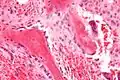

Osteoblasts (purple) rimming a bony spicule (pink - on diagonal of image). In this routinely fixed and decalcified (bone mineral removed) tissue, the osteoblasts have retracted and are separated from each other and from their underlying matrix. In living bone, the cells are linked by tight junctions and gap junctions, and integrated with underlying osteocytes and matrix H&E stain. | |